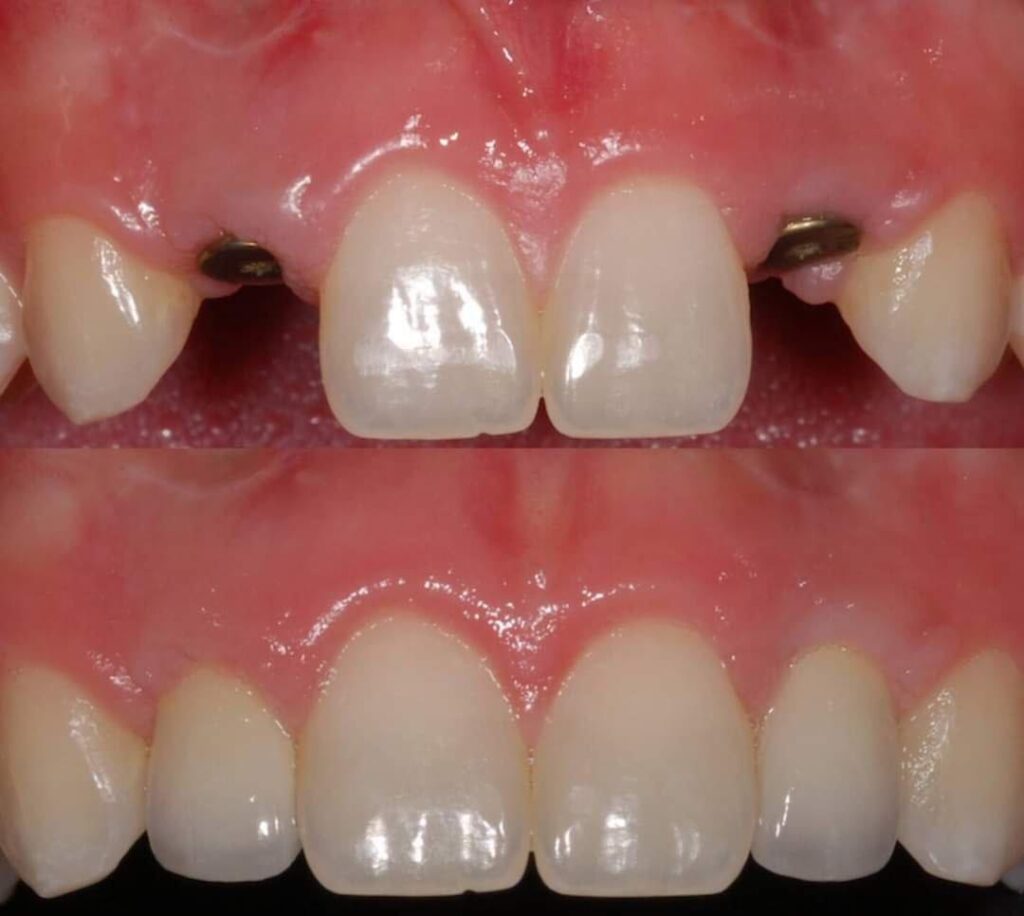

جماليات زراعة الأسنان

يتم تخطيط وتنفيذ إجراء زراعة الأسنان بعناية لضمان أن ترميم الأسنان يبدو طبيعيًا في الشكل واللون والمكان. نعطي الأولوية لراحة مرضانا بالإضافة إلى الجماليات. وهذا يتطلب مزيجًا مثاليًا من العبقرية الفنية والجراحية. لذلك ، يتم تنفيذ جميع حالات الزرع لدينا من قبل فريق من أطباء الأسنان التجميليين وأخصائي زراعة الأسنان.